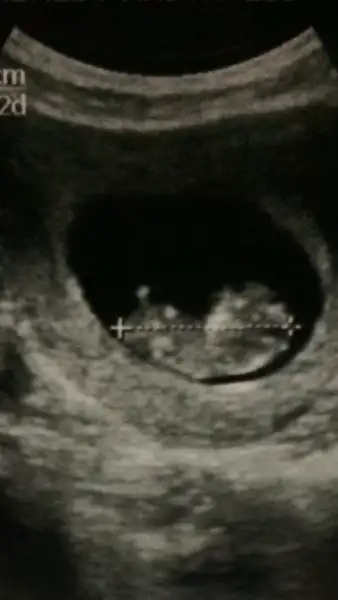

Canım benim tüp bebekle oldu başından beri nurettin bey takip ediyor sevgide , ona gitmeseydim de alattin bey e giderdim , en iyi cihazlar bu doktorlarda tavsiye ederim ..